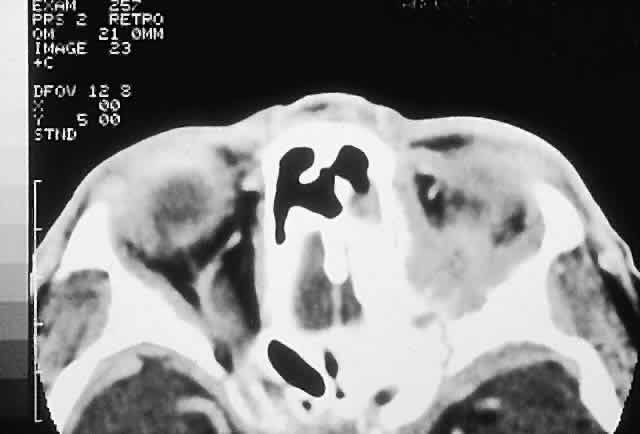

clinicopathologic classification (see Table 1). BENIGN FIBRO-OSSEOUS AND CARTILAGINOUS LESIONS Osteoma A true osteoma is a tumor-like mass of bony tissue that is histologically similar to normal bone. Its pathogenesis remains unclear, although traumatic, infective, or hamartomatous theories have been proposed.4 Others have suggested that osteomas arise exclusively at the junction of bones of cartilaginous and membranous origin.5 None of these theories account for the facts. The most common sites of origin are the paranasal sinuses, skull, and facial bone. The fact that osteomas were found in 0.42% (15 of 3510) of plain sinus radiographs reflects their prevalence.6 In the sinuses, 50% occur in the frontal sinus, with the ethmoid, maxillary, and sphenoid involved in descending order of frequency. Most orbital osteomas are secondary invaders from adjacent sinuses, but on occasion they arise primarily in the orbit. In contrast to the sinus distribution, however, orbital osteomas appear to have a roughly equal origin from the ethmoid, frontoethmoid, or frontal regions.7,8 This may reflect the relatively thin barrier to expansion posed by the medial orbital wall. The age range runs the gamut from 10 to 82 years, with the highest prevalence in the fourth and fifth decades. Males and females are represented equally.7–9 PRESENTATION. Most sinus osteomas are solitary and asymptomatic.6 However, when large enough to encroach on the orbits, a gradual evolution of proptosis or globe displacement over many years can occur (Fig. 1). There may be an associated headache as a result of expansion of the overlying cortex and periosteum, and a bony mass is often palpable in the superior or superomedial orbit. Obstruction of the sinus ostia may lead to chronic sinusitis or mucocele. Less common features include an acquired Brown syndrome,10 gaze-evoked amaurosis or pain,4,11 subluxation of the eye12 and erosion leading to orbital emphysema, or cerebrospinal fluid rhinorrhea.13 The sphenoid sinus, although a rare site, is significant because even a small lesion may lead to an orbital apex syndrome. An uncommon but important systemic association is Gardner's syndrome. This autosomal dominant syndrome of osteomas, soft tissue tumors, and peripheral congenital retinal pigment epithelial hypertrophy also includes the development of colonic polyposis with subsequent malignant transformation.14–16 Multiple osteomas are common; our one patient had only a single tumor, but one was also noted in the skull. Further, because bony lesions may predate the colonic pathology, patients with osteoma warrant a dilated funduscopy and referral to a gastroenterologist.17 IMAGING. The plain radiograph and CT appearances consist of an osteoblastic round or ovoid sharply circumscribed mass, usually arising in the sinus and invading the orbit. Tumors growing in a sinus conform to its internal contour and often have a bosselated surface. Osteomas may be sessile or pedunculated and generally have a diameter of 1 to 5 cm.18 Bone window settings on CT imaging often show a very dense periphery with a more cancellous internal structure. However, the relative proportions of the two densities may vary with the size of the lesion. HISTOPATHOLOGY. It is important to distinguish osteomas from reactive osteomatous responses to infection, trauma, and chronic inflammation. The clinical and radiologic appearances are often invaluable in this regard. Macroscopically, true osteomas have smooth or bosselated contours with a glistening white or pinkish coloration. A covering of mucoperiosteum or periorbita may be seen, depending on the site of origin.18 Osteomas have been classified histologically into three groups depending on the predominant tissue present: compact (cortical, ivory), cancellous (trabecular, spongy), and fibrous. Fu and Perzin19 have postulated that the histologic type is partly dependent on the age of the lesion, with the compact group representing the most mature and the fibrous the least. The fibrous subtype may, in fact, be part of a continuum incorporating ossifying fibroma and fibrous dysplasia. The compact areas resemble normal cortical bone with dense bony areas and haversian systems. However, there are subtle differences in the arrangement of the haversian canals, which is often evident to the experienced bone pathologist. The cancellous areas consist of anastomosing trabeculae with an intervening fibrovascular stroma. Fatty and hematopoietic elements may also be present in the stroma, as well as evidence of osteoblastic activity along the trabeculae. The fibrous region is made up primarily of loose fibrovascular tissue with a few irregular bony trabeculae and osteoid elements. In our series of nine surgically treated cases, we noted that although the three types of tissue were present in varying admixtures, in all cases there was a remarkably consistent pattern of arrangement. The most peripheral zone was made up of compact bone; moving toward the center or base of the lesion, there was an intermediate zone of increased osteoblastic activity, osteoid, and vascularity. The innermost region consisted of a loose fibrous stroma with a greater number of blood vessels, few trabeculae, and many plump osteoblasts. This configuration has been described previously by Albert and associates20 and illustrates the growth of these lesions. The outermost zone presumably represents more mature bone, and the activity seen centrally suggests that this is where growth is initiated. This implies that extirpation of the central region is probably required to prevent recurrence. It may also explain why leaving residual peripheral areas does not usually lead to regrowth. Finally, the histologic subtyping into compact, cancellous, and fibrous lesions probably has little practical significance, because there appears to be no correlation with the clinical course. MANAGEMENT. Generally, asymptomatic osteomas can be treated conservatively. The only possible exception to this is in the sphenoid sinus: it is technically easier to remove a small lesion in this location before it has encroached on the orbital apex and optic canal. If symptomatic and located in the anterior orbit, osteomas can be removed through an anterior orbitotomy. For anterior ethmoid tumors in the superomedial orbit, a modified Lynch incision is often used. Excision can sometimes be aided by coring the lesion and collapsing the cortex for removal. For more posterior tumors, involving the roof or cribriform plate, a combined orbitocranial approach using a bicoronal incision is favored.21 Recurrence is rare, even after a partial resection. Fibrous Dysplasia Fibrous dysplasia is a benign disorder in which proliferation of fibrous tissue and osteoid replaces and distorts medullary bone. The cause is unknown; past theories have included a maturation arrest at the woven bone stage, or hamartomatous proliferation.22 More recently, the discovery of a postzygotic mutation in the G protein in McCune-Albright syndrome suggests that the bone dysplasia in these patients is a manifestation of a somatic mosaic state.23,24 There are three forms of fibrous dysplasia: monostotic fibrous dysplasia (MFD), polyostotic fibrous dysplasia (PFD), and McCune-Albright syndrome.22,25 MFD accounts for 75% to 80% of cases, of which 20% affect the craniofacial bones. In the skull, the frontal bone is most commonly involved, followed by the sphenoid and ethmoid. Most patients with orbital involvement have MFD, although the disease has generally spread to contiguous bones by the time the patient comes to medical attention. PFD makes up 20% of all cases; half of these patients have head and neck involvement. McCune-Albright syndrome occurs largely in females and incorporates the triad of PFD, sexual precocity, and cutaneous pigmentation.26 This pigmentation appears as brown macules, usually six or fewer, with irregular “coast of Maine” borders.27 Fibrous dysplasia is generally recognized before age 30, although mild or asymptomatic cases may escape detection into late adult life.28 The gender distribution is roughly equal in MFD; there is a female predilection in PFD. PRESENTATION. The site and the extent of disease are the major determinants of symptomatology. Facial asymmetry, proptosis, and globe displacement evolving over many years are the most common manifestations (Fig. 2). Nasolacrimal duct blockage, diplopia, nasal obstruction, malocclusion, raised intracranial pressure, and cranial nerve palsies also occur.25,28–30 Acute or subacute compressive optic neuropathy can arise as a result of intralesional hemorrhage, sphenoidal mucocele, or secondary aneurysmal bone cyst.31 A more chronic visual loss, although less commonly reported, may occur as a result of compression in the optic canal or at the chiasm. On occasion, a superimposed ischemic neuropathy in the context of chronic compression leads to an acute on chronic deterioration in vision.32 This clinical spectrum is reflected in our experience of 10 cases. Changes in facial contour (7 patients), proptosis (7), globe dystopia (6), and decreased vision (3) were the major signs. Interestingly, seven patients also had pain, either localized to the orbit or described as a diffuse ipsilateral headache. Overall, the natural history is one of slow growth. Although this was previously thought to cease in adult life, there is evidence that fibrous dysplasia may progress well past the fourth decade.25 Rarely, malignant transformation to osteosarcoma, fibrosarcoma, chondrosarcoma, and giant cell sarcoma can occur; this is often signaled by a more rapid progression and increased pain. The incidence of this complication is estimated at 0.4% to 0.5%, rising to approximately 15% with prior radiation therapy.33 IMAGING. In the craniofacial bones, fibrous dysplasia tends to expand the bone, with thinning of the overlying cortex. The margins are poorly defined, and the dysplasia transgresses suture lines; the proportion of mineralized to fibrous tissue determines the degree of radiolucency. Most cases demonstrate a relatively equal mixture, resulting in a pagetoid appearance. Where the fibrous element is predominant, there may be cystlike areas; a preponderance of mineralized tissue, however, results in a homogeneous, sclerotic, “ground-glass” picture. Fries34 reviewed 39 patients with fibrous dysplasia of the craniofacial bones and found a pagetoid pattern to be most common (56%), followed by sclerotic (23%) and cystlike (21%) appearances. The primary differential is hyperostotic meningioma. This is distinguished by its occurrence in an older age group and by the presence of an associated enhancing soft tissue component, best seen on MRI. Also, meningioma often causes a more homogeneous thickening of bone, which in contrast to fibrous dysplasia does not leave a discernible cortical rim. MRI shows meningioma to have a signal isointense to gray matter on both T1- and T2-weighted images. Fibrous dysplasia, in contrast, tends to have a lower intensity on T1- and a heterogeneous signal on T2-weighted images.28,35 MRI may also have a role in fibrous dysplasia in the evaluation of mucoceles and recent hemorrhage. On occasion, Paget's disease and less commonly cystic bone lesions, such as localized Langerhans cell histiocytosis (eosinophilic granuloma), also enter into the differential diagnosis. Paget's disease arises beyond the age of 40, is usually bilateral, and radiologically may show areas of cotton wooltype density that are not usually seen in fibrous dysplasia. HISTOPATHOLOGY. Macroscopically, fibrous dysplasia consists of gritty, white-to-pink tissue, often with blood or serous-filled cystic areas. Histologically, there is a fibrous background containing trabeculae of woven bone. The stroma has variable amounts of collagen, fibroblasts, and vascularity. There may also be myxomatous areas and secondary aneurysmal bone cysts. The curvilinear bone trabeculae take on a variety of configurations, including C or Y shapes (so-called Chinese characters). These trabeculae sometimes have irregular margins as a result of the attachment of collagen fibers arising in the stroma. Cartilaginous nodules as well as small foci of lamellar bone are occasionally seen, but the vast majority of lesions contain immature woven bone. At its periphery, fibrous dysplasia permeates normal bone, and there may be areas of reactive bone with more prominent lamellar bone formation and osteoblastic rimming. Sequential biopsies of fibrous dysplasia from childhood to adult life have shown that the histologic picture does not change with time.36 In the skull, the major histologic differential is ossifying fibroma. The latter, however, is a more circumscribed lesion that displays prominent production of lamellar bone with osteoblastic rimming. MANAGEMENT. Traditionally, there has been a conservative approach to surgery for fibrous dysplasia, with intervention reserved for gross deformity, functional deficits, pain, or sarcomatous transformation. The procedures included resection if the lesion was well localized, curettage with bone grafting, or contouring. The last two decades have seen a shift to more aggressive and earlier intervention. A multidisciplinary craniofacial approach has been advocated, wherein as much affected bone as possible is removed and the resulting defects are reconstructed in a single operation.37 The indications for intervention include those previously mentioned, with the added rationale of attempting to prevent complications such as optic nerve compression.23,38 However, long-term follow-up data comparing outcomes with the natural history of the disease are lacking. Also, there have been two reports of blindness complicating prophylactic optic nerve decompression.25,32,39 Thus, the need for prophylactic treatment remains unresolved; it is not recommended unless a functional deficit develops. Ossifying Fibroma There is controversy as to whether ossifying fibroma is a distinct clinicopathologic entity: some authors believe it is a variant of fibrous dysplasia.40 Nevertheless, there appear to be enough disparate features to characterize it as a benign fibro-osseous neoplasm. Ossifying fibroma occurs most commonly in the mandible in the first two decades of life, with a proclivity for females. Only rarely does it arise in the orbit, with the frontal bone being most commonly involved, followed by the ethmoid and the maxillary bones. There are 37 orbital cases reported in the literature, with an age range of 4 months to 52 years and an approximately equal male/female ratio.12,19,41–50 PRESENTATION. As a result of its slow growth, ossifying fibroma generally manifests as a gradual painless globe displacement, with a temporal course measured in years. The mass effect may also lead to proptosis, diplopia, and, if situated more posteriorly, compression of apical structures. IMAGING. Ossifying fibroma starts as a monostotic lesion that expands the bone of origin in a well-circumscribed manner. However, with growth it may spread to involve adjacent bones and may even extend across the midline to involve both orbits. The characteristic CT appearance is of a round or ovoid mass with a well-defined, thin sclerotic margin (Fig. 3). Centrally, there is often a patchy pattern of osteoblastic and osteolytic areas.46 HISTOPATHOLOGY. Macroscopically, the lesional tissue is white to red and has a largely soft fibrous texture with variable grittiness, dependent on the amount of osteoid. Microscopically, it consists of a cellular vascular stroma containing trabeculae of lamellar bone. These bony trabeculae often have a thin surrounding of osteoid and, in contrast to fibrous dysplasia, display prominent osteoblastic rimming. There may also be osteoblasts as well as a few foci of giant cells in the stroma. If larger specimens are available, they may demonstrate a zonation phenomenon, seen as an increasing maturity of bone toward the periphery.19 In the psammomatoid variant described by Margo and colleagues,49 at least half of the tumor contains sphericular ossicles. This histologic pattern has been correlated with a more aggressive local behavior and a tendency to recur after incomplete excision. MANAGEMENT. The natural history of ossifying fibroma is one of inexorable progression; thus, surgical intervention is generally required. Because the propensity for recurrence after incomplete excision is well recognized, the surgical objective should be complete removal. This is particularly applicable in the psammomatoid variant. For anterior, relatively small lesions, this may be achieved using a percutaneous or bicoronal approach. However, most tumors tend to be sizable (5 cm in diameter) at presentation.49 Thus, for these lesions as well as those located more posteriorly, combined orbital, neurosurgical, and rhinologic approaches are usually necessary.45 Osteoblastoma Osteoblastoma is a benign tumor composed of osteoblasts that produce osteoid and bone. It usually arises in the vertebrae and long bones, and its occurrence in the craniofacial region is extremely rare. These tumors are most commonly seen in the second and third decades and have a male/female ratio of 2:1.51 Seven cases with orbital involvement have been reported in the past 30 years.19,52–57 In four of these, the tumors appeared to arise from the orbital roof, with the remainder originating in the ethmoid sinuses. The natural history is of slow growth, although a minority display a more aggressive behavior (aggressive osteoblastoma). PRESENTATION. The presentation in all patients was of a slowly progressive mass effect with proptosis and either downward or outward displacement of the globe. Pain or discomfort was a feature in several patients. IMAGING. In the long bones, osteoblastomas produce cortical expansion and have a lytic center. They can also simulate a large osteoid osteoma, with a lucent halo and central ossification. The different morphology of the orbital bones means that the tumor appears as an osteolytic lesion with a sclerotic margin; it occasionally has ossification of the matrix.51 HISTOPATHOLOGY. The gross appearance is of a relatively gritty or friable, reddish-brown tissue. There is a broad spectrum of histologic appearances. The typical picture is of a network of osteoid trabeculae with osteoblastic rimming. These osteoblasts generally have abundant cytoplasm and regular nuclei. However, in some tumors, large epithelioid osteoblasts or a pseudosarcomatous appearance can be observed; this can lead to confusion with osteosarcoma.58 In contrast to osteosarcomas, however, even atypical osteoblastomas show a tendency toward peripheral maturation and do not permeate surrounding bone. Some authors have suggested that this atypical appearance may correlate with a more aggressive clinical course and have used the term aggressive osteoblastoma to define a separate clinicopathologic entity. It is a rare variant, with only one case being reported in the skull.59 The histology of osteoblastoma is similar to that of osteoid osteoma, with the latter being distinguished by a size smaller than 1.5 cm as well as a somewhat less cellular and vascular stroma.60 Nevertheless, they may represent a spectrum of disease, a fact somewhat supported by the recent finding of a common clonal chromosomal abnormality in both tumors.61 Osteoid osteoma, however, has not been reported in the orbit. MANAGEMENT. Excision is generally curative; however, there is one report of recurrence of an orbital tumor after a piecemeal removal.56 There have also been descriptions of a benign osteoblastoma of the skull that developed into an osteosarcoma after an incomplete excision,62 as well as a case of aggressive osteoblastoma of the temporal bone.63 In view of this, osteoblastomas should be completely removed under direct vision, where possible, to determine the margins. This usually entails an orbitocranial approach for tumors of the roof and a combined orbitorhinologic approach to those arising in the sinuses. Chondroma These benign cartilaginous tumors usually occur as asymptomatic lesions in the sinuses and nasal cavity. They rarely occur in the orbit, where they present as slow-growing, painless, firm lumps, often near the orbital rim or the trochlea.64,65 They have on occasion also been described in the soft tissues of the orbit.66 Radiologically, they are seen as well-circumscribed, dense masses that histologically consist of lobulated mature hyaline cartilage. Mature chondrocytes are seen in the cartilage, along with a variable fibrous or myxoid stroma. Surgical excision is always curative.64,67 A variety of other benign cartilaginous tumors, including osteochondromas, enchondromas (Fig. 4), and fibrochondromas, have also rarely been described in the orbit, although the histologic documentation is not always convincing.68 REACTIVE LESIONS Cholesterol Granuloma A cholesterol granuloma is a foreign body response to the presence of crystallized cholesterol. The common sites are the middle ear and pneumatized portions of the temporal bone.69 In the orbit, it occurs almost exclusively in the diploë of the frontal bone overlying the lacrimal fossa, although it has also been reported in the zygoma.70 Theories of pathogenesis include a purely traumatic intradiploic hematoma or a hemorrhage occurring in a pre-existing bony anomaly. A breakdown of blood products then leads to cholesterol deposition and a granulomatous response. An analysis of 75 reported cases of orbital cholesterol granulomas revealed a marked preponderance of men in the fourth and fifth decades of life.70,71 PRESENTATION. A superolateral mass effect encompassing weeks to years is the typical mode of presentation. This leads to inferior globe displacement, proptosis, and diplopia in upgaze (Fig. 5). There may be associated headache or pain; one third of patients recall a prior trauma.70,71 IMAGING. The granuloma arises in the diploë of the frontal bone, causing expansion and eventually erosion of the inner and outer tables. CT reveals it to be osteolytic, with a density equivalent to brain, and occasional intralesional bone fragments.72 Mature lesions display high T1 and T2 signal intensities on MRI.73,74 The most commonly evoked differentials in this setting are dermoid cysts and lacrimal gland carcinomas. HISTOPATHOLOGY. These cysts usually contain yellow-brown viscous material with friable tissue and porous bone at the periphery. Histologically, the principal feature is the dominance of cholesterol clefts surrounded by granulomatous inflammation with conspicuous foreign body giant cells. A variable fibrous stroma is present and usually contains extensive blood-derived debris in the form of extracellular and intracellular hemosiderin as well as more recent hemorrhage.70,75 There should be no evidence of epithelial elements, ruling out a diagnosis of epidermoid or dermoid cyst. The prominence of the xanthomatous components also serves to differentiate this condition from giant cell granuloma and aneurysmal bone cyst. We have seen six cases of cholesterol granuloma, two of which had histologic evidence of dysplastic-looking bone at their peripheries. This perhaps lends some support to the theory of a pre-existing dysplastic bony abnormality. MANAGEMENT. A percutaneous approach and curettage is almost always curative, with only one well-documented case of recurrence that occurred when peripheral bone containing lesional tissue was not removed.71 If there is an extensive intracranial component, a combined orbitocranial operation may be required.76 Aneurysmal Bone Cyst This benign cystic lesion occurs most commonly in the metaphyses of long bones and in the spine. The pathogenesis is not known, although 30% to 50% occur secondary to other bone diseases, including fibrous dysplasia, giant cell granuloma, giant cell tumor, osteoblastoma, osteosarcoma, and intraosseous hemangioma.18,77,78 There is also evidence that some aneurysmal bone cysts (ABCs) may arise as a reactive change to a pre-existing arteriovenous malformation.40 ABCs occur rarely in the skull; of those with orbital involvement, the frontal bone appears to be the most common location. An analysis of 24 recorded orbital cases, including 2 from our series, revealed an age range of 11 months to 42 years. Most presented in the second decade, and there was a female preponderance of 5:3.8,78–89 PRESENTATION. The usual signs and symptoms include proptosis, displacement of the eye, and diplopia. Masses in the midline can cause optic nerve compression.82 Because most ABCs arise in the orbital roof, intracranial extension can rarely give rise to raised intracranial pressure. Although typically subacute or chronic in evolution, sudden progression may occur as a result of intralesional hemorrhage.83 IMAGING. ABCs occurring in long bones have a characteristic uni- or multilocular expansile appearance. However, the radiology in the orbital bones is not specific and consists of destruction or expansion (Fig. 6). If expansile, the mass may have a thin cortical margin, but this is often absent as a consequence of erosion through to periorbita or dura. The central area is inhomogeneous, shows patchy enhancement, and can have multiple fluid levels, particularly in the more mature lesions.85,88 MRI may demonstrate recent hemorrhage in cases with an acute onset. HISTOPATHOLOGY. The gross specimen almost always consists of curettings of reddish-brown tissue with a texture that varies from friable to fibrous or gritty. More solid lesions may yield softer, pink to gray-white tissue. If larger samples are available, one may see honeycombed areas of serosanguineous or blood-filled cavitation.18,40 The cardinal microscopic features are cavernous blood-filled spaces that lack endothelial lining, pericytes, or smooth muscle. These spaces are bounded by a fibrous stroma that contains giant cells, hemosiderin-laden macrophages, lymphocytes, and trabeculae of osteoid and bone. The osteoid may lack osteoblastic rimming and may seem to arise from the stroma in a metaplastic fashion. Degenerating chondromyxoid areas may surround the osteoid and can display partial calcification.18,40 In 1983, Sanerkin and coworkers90 described a solid variant of ABC in which the aneurysmal sinusoids were either seen only in small foci or were absent. We have seen two cases that fit this histologic description. It is evident that this picture, apart from the chondromyxoid and sinusoidal foci, may bear a close resemblance to giant cell granuloma. Finally, in any case of ABC, one should conduct a meticulous search for a primary pathology such as fibrous dysplasia. MANAGEMENT. Curettage is typically curative. In the absence of an underlying bony abnormality, recurrence of orbital lesions is rare and usually occurs in the first 6 months.77,85 In such cases, a repeat curettage is generally successful. Resolution has also been reported after incomplete excisions. Radiation therapy has been used for recurrent aggressive lesions, but it entails a small yet definite risk of postradiation sarcoma.77 Giant Cell Granuloma Giant cell granuloma (GCG) is a benign granulomatous proliferation of unknown cause. It has also been called giant cell reparative granuloma, the term referring to a past theory postulating a reparative process in response to trauma and hemorrhage.91 GCG occurs most commonly in the mandible, maxilla, and phalanges.92 Cases with orbital involvement have been reported rarely and appear to have arisen in the maxilla, frontal, ethmoid, and sphenoid bones with equal frequency. Nine patients are reported in the literature and with the inclusion of our patient, they range in age from 5 to 54 years (average 18.6 years), and the male/female ratio is 3:2.93–98 This corresponds with the epidemiology of GCG elsewhere in the skeleton, which generally presents in the first two decades of life with an equal male/female ratio.94,96 PRESENTATION. Proptosis and ocular displacement are the most common presentations, although headache and pain may be prominent (Fig. 7). Diplopia and decreased vision also occur, depending on the site of the mass. The time course is variable, ranging from months to years, and may be complicated by a rapid progression of symptoms resulting from hemorrhage. IMAGING. GCG typically manifests as a destructive lesion with erosion of adjacent bone. It may have indistinct or sclerotic margins and may show moderate enhancement of an often-inhomogeneous central matrix. HISTOPATHOLOGY. Macroscopically, the granuloma consists of soft, friable, tan to brown tissue, typically in the form of curettings. A fibrous stroma with giant cells clustered around foci of hemorrhage is the dominant histology. This stroma contains ovoid and spindle-shaped fibroblasts with a variable amount of fibrosis and evidence of old and new hemorrhage. Reactive bone formation is common (75%) and consists of trabeculae of woven and lamellar bone, which may or may not demonstrate osteoblastic rimming. Areas of secondary aneurysmal bone cyst formation may also be seen.91,92,95 When the preceding histologic pattern is seen, investigations to exclude Brown tumor of hyperparathyroidism are necessary. Once the latter diagnosis is ruled out, the histologic differential includes giant cell tumor and the solid areas in an ABC. It is important to differentiate giant cell tumor from GCG because the former is more aggressive and can undergo malignant transformation. Hirsch and Katz92 have outlined the histologic criteria for this differentiation. The major differences are that in giant cell tumor, the stroma is made up of largely plump, round, oval cells, and it displays less fibrosis than the often spindle-cell stroma of GCG. Also, the giant cells in giant cell tumor tend to be larger with more nuclei (more than 20) and are more diffusely distributed, rather than being centered around hemorrhagic foci, as in GCG. In addition, reactive bone formation is not a conspicuous feature of giant cell tumor. Nevertheless, the distinction between the two entities is not always sharply delineated. MANAGEMENT. GCG generally responds well to curettage with or without bone grafting. A variable recurrence rate is reported for lesions elsewhere in the body, but most appear to be cured with a second curettage. This generalization appears to hold true for most orbital cases. However, in one patient described by Sood and colleagues,93 the tumor behaved in a locally aggressive fashion, requiring three operations and ultimately radiation therapy. “Brown Tumor” of Hyperparathyroidism “Brown tumor” represents a benign reactive proliferation with a histologic appearance virtually identical to GCG. Its association with primary or secondary hyperparathyroidism, however, differentiates the former. Brown tumors arise as a consequence of the increased osteoclastic activity associated with hyperparathyroidism. This leads to focal areas of bone resorption and hemorrhage. Histologically proven orbital Brown tumors have been described in 14 cases in the literature.8,12,99–108 They appeared in an older age group (range, 10 to 70 years; average 33 years), with a more marked female preponderance (5:2) when compared with GCG. Eight cases were associated with primary hyperparathyroidism and six with hyperparathyroidism secondary to renal dysfunction. The maxilla and the frontal bone were the favored sites, in that order. Brown tumors tend to have a temporal onset usually measured in months and like GCGs are vulnerable to intralesional hemorrhage. Patients with Brown tumors also demonstrate abnormalities in serum calcium, phosphate, alkaline phosphatase, and parathormone levels and skeletal surveys.108 The radiologic and histologic appearances are essentially the same as for GCG (Fig. 8). Treatment of the hyperparathyroidism often results in spontaneous resorption and healing of the bony lesion.12,105,108 Hence, a careful clinical evaluation for manifestations of hypercalcemia or renal dysfunction may obviate the need for surgery. NEOPLASMS Osteosarcoma Osteosarcoma (osteogenic sarcoma) is the most common primary neoplasm of bone. Long bones are the most common site; orbital involvement is rare and usually from a maxillary focus. In most cases, the tumor arises de novo, but some are secondary to Paget's disease, fibrous dysplasia, radiation therapy, giant cell tumor, or osteoblastoma.40 Osteosarcomas are also seen as a second tumor in patients with familial retinoblastoma, even in the absence of radiation therapy. Also, a proportion of de novo osteosarcomas have been found to share the deletion of chromosome 13, which renders the retinoblastoma antioncogene inactive.109–112 De novo tumors are most common in the second decade, with a slight male predilection; however, osteosarcomas involving the orbit afflict an older population, being most common in the fourth and fifth decades (range, 10 to 54 years). The common precursor lesions for secondary tumors in the orbit appear to be radiation therapy, Paget's disease, and fibrous dysplasia.12,113–115 PRESENTATION. The course is typically more rapid than that of the benign tumors discussed previously, averaging approximately 4 to 6 months. In addition to any mass effect, there may be significant pain and infiltration leading to diplopia and decreased vision. IMAGING. A mixed lytic and sclerotic mass with indistinct margins is the usual CT appearance (Fig. 9). Soft tissue infiltration of the orbit may also be evident, and the mass may contain foci of mineralization, producing fluffy densities. MRI can be of value in delineating the extent of any soft tissue component.12,116,117 HISTOPATHOLOGY. Gross specimens contain infiltrative tumor, which may be white, tan, or hemorrhagic in parts, with a soft to firm or gritty texture, depending on the stromal components. The stroma contains sarcomatous cells and must show at least some foci of osteoid production. The anaplastic cells may subsume a variety of histologic subtypes, including osteoblastic, chondroblastic, and fibroblastic. In most high-grade lesions, the cells are markedly malignant, but they become less so when incorporated into the osteoid (so-called normalization of malignant osteoid). The osteoid itself may assume a characteristic delicate filigreed or lacelike pattern.40 MANAGEMENT. The regimen for osteosarcoma involves preoperative chemotherapy, resection, and then continuation of the chemotherapy, with modifications based on the pathology of the resected specimen. Radiation therapy has an adjunctive postoperative role for residual tumor. These therapies have improved the 5-year survival rate from 20% to 70% for resectable lesions.118 However, the prognosis in the skull is poorer because of delayed diagnosis and inability to obtain complete resection once the tumor has gained access to the skull base or intracranial space.116,117 Chondrosarcoma This malignant tumor is characterized by chondroid production and occurs most commonly in the lower extremities and pelvis. Orbital involvement is generally secondary to tumors arising in the sinuses and nasal cavity. Craniofacial chondrosarcomas have a male/female ratio of 2:1 and are prevalent in the fifth and sixth decades, with a wide age range.20,65,119–122 PRESENTATION. Because of their frequent sinus origin, chondrosarcomas usually manifest symptoms of nasal and sinus obstruction.65,123,124 Orbital mass effects often occur medially or inferiorly and consist of proptosis, ocular displacement, and epiphora secondary to nasolacrimal duct obstruction. There may be a variable degree of pain or headache as well as infiltrative features. Posterior growth leads to compromise of the optic nerve and apical structures. The course is usually prolonged, and symptom duration averages 2 to 3 years. IMAGING. Chondrosarcomas appear as well-defined osteolytic lesions with stippled or mottled densities indicative of mineralization (Fig. 10). Higher-grade tumors tend to have irregular margins with nonuniform calcification in the form of amorphous cloudlike densities.125 The noncalcified regions show T1 signal intensities lower than or equal to gray matter on MRI. T2 signals are isointense to the cortex, and the masses usually display moderate enhancement.121,124,126,127 HISTOPATHOLOGY. Grossly, the tissue is white to blue-gray, with a discernible lobular pattern. Histologically, there are irregular lobules of hypercellular cartilage with lacunae containing plump bi- or multinucleated chondrocytes, separated by fibrous stroma or reactive bony trabeculae. The stroma may be myxoid in areas and shows a wide variability in the amount of cellularity, atypia, and chondroid matrix, which has led to a grading system. The grades 1 through 3 appear to have some correlation with prognosis.119,121,128 This is manifest in tumors involving the orbit, which are mostly grades 1 or 2 and exhibit slow growth with a low incidence of metastasis. The major histologic differentials for conventional chondrosarcomas in the orbit are chondromas and chondroblastic osteosarcomas. MANAGEMENT. Ablative surgery is the goal for resectable chondrosarcomas. However, for craniofacial tumors, this is often not possible, and because of their indolent growth a protracted course with multiple recurrences is common. Although not particularly radio- or chemosensitive tumors, both these modalities have been used in an adjunctive role for incompletely excised lesions.121,124 We have treated two cases of extensive grade 2 chondrosarcoma with radical debulking and postoperative radiation therapy. Both patients have no evidence of recurrence after 14 and 11 years, respectively. Mesenchymal Chondrosarcoma Mesenchymal chondrosarcoma is a variant of chondrosarcoma that commonly arises in the jaw. In the orbit, it favors the soft tissues, although bony involvement can occur. It occurs in a younger age group and in the orbit has a female predilection.122 In contrast to conventional chondrosarcoma, this tumor progresses more rapidly and presents with proptosis and infiltrative effects of less than a year's duration. Radiologically it appears on CT as a nonspecific, irregular, mottled, soft tissue mass; the MRI characteristics are similar to the noncalcified areas of the conventional type.127 Histologically, the mesenchymal variant consists of lobules of cartilage arising in a highly cellular stroma of malignant, small round cells. The chondroid production serves to differentiate it from other small round cell tumors, such as Ewing's sarcoma. Because of its origin in the soft tissues, mesenchymal chondrosarcoma is typically treated with exenteration. Despite the small number of reported orbital cases, it appears that resection is adequate therapy in certain patients. More recent reports suggest that mesenchymal chondrosarcoma may also be successfully managed by local resection with adjuvant chemo- and radiotherapy, thus obviating the need for exenteration.129 Compared with the conventional type, however, it has a more rapid course and a propensity for early spread, particularly to the lungs. Ewing's Sarcoma Ewing's sarcoma is a small round cell tumor that usually arises in bone. The characteristic chromosomal translocations (t(11;22)(q24:q12)) and proto-oncogenes expressed in this neoplasm suggest an undifferentiated neuroectodermal tumor.130,131 Most cases arise in the first two decades, with a predilection for males (1.5:1). The tumor is uncommon among blacks. Incidence in the head and neck is approximately 4% and favors the mandible and maxilla.18,132 Most orbital cases represent metastases or direct extension, with only a handful of primary orbital lesions reported.133–135 Hence, an orbital presentation should institute a rigorous search for a primary. PRESENTATION. Nonaxial proptosis of relatively short duration is the usual presentation. We have encountered two cases of primary orbital Ewing's sarcoma, in patients 6 and 10 years old, respectively. Both boys had a 4-week history of ocular displacement. One tumor arose from the maxilla, the other from the nasopharynx. IMAGING. The CT appearance is of an expansile or permeating mass that shows mottled bone destruction (Fig. 11). There may be an associated soft tissue component. HISTOPATHOLOGY. The tumor consists of firm, white tissue made up microscopically of sheets and clusters of uniform, small round cells. Cytoplasmic glycogen, as demonstrated by periodic acid-Schiff (PAS) positivity, is present in 90% of cases. Ultrastructurally, there is evidence of glycogen and a sparsity of organelles.18 The criteria for distinguishing Ewing's from neuroectodermal tumor of bone have not been well elucidated. In broad terms, however, Ewing's should not demonstrate signs of neuroectodermal differentiation on light or electron microscopy. Although they probably reflect different points in a spectrum of differentiation, the distinction continues to be made, in part because of the poorer prognosis of the neuroectodermal tumors of bone.136 The other differentials to be considered are metastatic neuroblastoma and chloroma in patients younger than 5 years of age and lymphoma in older patients. Mesenchymal chondrosarcomas and the small cell variant of osteosarcoma are distinguished primarily by the appropriate matrix production. MANAGEMENT. Induction multiagent chemotherapy followed by radical local surgery or radiation therapy has resulted in improved 5-year survival rates of up to 74%. Unfortunately, 17% to 20% of survivors subsequently develop a second primary, most commonly osteosarcoma.137,138 As a result of factors such as improved local control and postradiation malignancies, surgery is currently favored over radiation therapy for resectable lesions.139 Hematopoietic and Histiocytic Lesions MYELOMA. Multiple myeloma and more rarely solitary plasmacytoma may involve orbital bone.140–143 These tumors affect those older than 50 years and present with a subacute onset of pain and proptosis. In the case of multiple myeloma, there are usually systemic manifestations such as bone pain, fever, and fatigue, as well as urinary and serum protein abnormalities. Radiologically, an osteolytic area with a contiguous soft tissue mass is the rule. Histologically, the tumors are composed of broad sheets of malignant plasma cells varying in appearance from mature to blastlike.40 LANGERHANS CELL HISTIOCYTOSIS. Langerhans cell histiocytosis consists of a variety of syndromes resulting from the proliferation of Langerhans cells. Localized bone involvement (eosinophilic granuloma) is prevalent in boys ages 3 to 10 years. These children characteristically develop proptosis as a result of focal lytic superolateral lesions associated with soft tissue expansion.144–146 We have seen six cases of localized Langerhans cell histiocytosis, and each demonstrated a characteristic CT appearance of a central radiolucent area with an enhancing rim (Fig. 12). Histologically, there is a granulomatous and histiocytic infiltrate with Langerhans cells and prominent eosinophils.147 Localized periorbital disease is responsive to curettage, intralesional steroid injections, or low-dose radiation therapy. The prognosis is poorer in younger patients with visceral involvement. Giant Cell Tumor Giant cell tumor is usually found in the long bones in the third to fifth decades, with a slight female predominance.40 It rarely occurs in the sphenoid, temporal, or ethmoid bones, with a primary orbital site reported on one occasion.52 Most cases with orbital involvement originate in the sphenoid; patients present with headaches, diplopia, decreased vision, and multiple cranial nerve palsies.148,149 The sphenoidal lesions are radiologically apparent as either lytic or soft tissue masses eroding the sella. This friable tumor is composed of uniformly distributed osteoclast-like giant cells. Occasionally, a giant cell tumor may display clinical and histologic evidence of malignancy and metastasize to the lungs.19,67 There is a 30% to 50% recurrence rate after curettage, so the goal is complete excision if possible. Radiation therapy has been reserved for inaccessible lesions because of the risk of inducing malignancy.148,149 VASCULAR TUMORS Aside from one report of a hemangioendothelioma of orbital bone, the only other vascular bony tumor described in the orbit has been the hemangioma. The hemangioendothelioma presented as an aggressive and lytic infiltrative lesion that recurred after resection.150 Intraosseous Hemangioma These benign vascular tumors of bone, like their counterparts in the orbital soft tissues, are probably hamartomatous in origin. They are common in the calvarium and spine but rare in the orbit. Any of the orbital bones may be involved, although the frontal bone is the most common site. Including one case of our own, there are 20 cases in the literature. The average age is in the fifth decade, with a slight female preponderance.151–155 PRESENTATION. A slowly developing orbital mass, often associated with pain or tenderness, is typical. There may be a palpable mass in the anterior orbit. IMAGING. Intraosseous hemangiomas present as well-defined, radiolucent masses that expand the inner and outer tables of the bone, often in an asymmetric fashion. Approximately half show the classic picture of a sunburst, striated, or honeycombed internal pattern (Fig. 13). On selective angiography, they appear as a tangle of vessels.155 HISTOPATHOLOGY. The specimen consists of soft, violaceous masses with intervening trabeculae of reactive bone. Microscopically, most are cavernous hemangiomas with large endothelial-lined, blood-filled vascular spaces.156 MANAGEMENT. Surgical treatment consists of excision with a rim of normal bone. Preoperative angiography should be performed and strong consideration given to embolization before resection, because these tumors can bleed in a profuse and persistent manner.155 MISCELLANEOUS There have been two reports of intramedullary lipoma of the frontal bone that led to chronic painless expansion simulating fibrous dysplasia.157 There have also been reports of intraosseous myxoma presenting in a similar fashion.158,159 Both malignant fibrous histiocytoma and fibrosarcoma can rarely arise in orbital bone, often as postradiation neoplasms.160–163 |